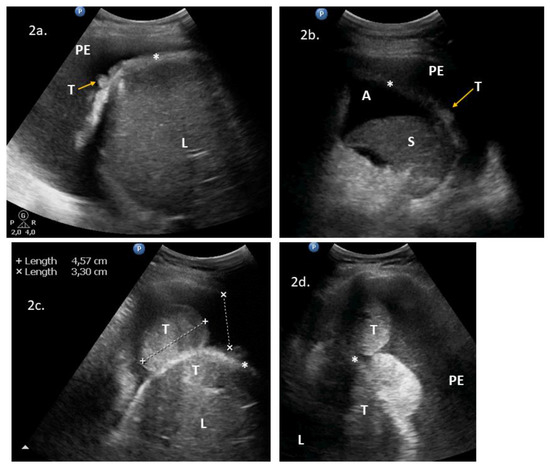

| No. | Age | PS | TAS/TVS | LUS/ICAUS | CT | Upstaging (IIIC → IV) with LUS/ICAUS Added to TAS/TVS? | Additional Procedures Planned after LUS/ICAUS? | LUS/ICAUS Added to TAS/TVS Changed Predicted Surgical Complexity [2]? | VATS Necessary? | Figure VS | Management /Comments |

|---|---|---|---|---|---|---|---|---|---|---|---|

| 1 | 71 | 3 | ascites, massive pelvic involvement, omental involvement, spleen involvement | pleural diaphragm involvement *, pleural effusions | ascites, carcinomatosis, massive pelvic involvement, omental involvement, pleural effusions, spleen involvement | Yes | Yes | NoScore: 9 → 11 High → High | Could replace DLSK | 2a | DLSK, HGSOC, NACT |

| 2 | 62 | 1 | ascites, carcinomatosis, omental involvement, spleen involvement | abdominal diaphragm involvement **, pleural effusions, ligamentum teres of the liver involvement | - | Yes | Yes | YesScore: 6 → 8 Intermediate → High | Could precede PDS | 2b, VS1 | PDS attempt. HGSOC, R > 1 cm |

| 3 | 53 | 3 | ascites, massive pelvic involvement, omental involvement | abdominal diaphragm involvement **, pleural diaphragm involvement *, pleural effusions | - | Yes | Yes | YesScore: 6 → 8 Intermediate → High | No | 2c, 2d, 3a, VS2 | PDS, mucinous G3. R = microscopic |

| 4 | 48 | 3 | ascites, carcinomatosis, massive pelvic involvement, omental involvement | abdominal diaphragm involvement **, other *, pleural effusions | ascites, abdominal diaphragm involvement, carcinomatosis, massive pelvic involvement, other *, omental involvement, pleural effusions | Yes | Yes | YesScore: 7 → 9 Intermediate → High | No | 3b, 4c, 4d, VS3 | PDS attempt because of low bowel obstruction symptoms. HGSOC, R > 1 cm. * suspected enlarged cardiophrenic lymph nodes |

| 5 | 79 | 3 | ascites, carcinomatosis, omental involvement | abdominal diaphragm involvement **, pleural effusions, spleen involvement | - | Yes | Yes | Yes Score: 4 → 8 Intermediate → High | No | 3c, 3d, VS4 | DLSK, HGSOC, NACT |

| 6 | 60 | 1 | massive pelvic involvement, omental involvement | abdominal diaphragm involvement **, spleen involvement, | - | Yes | Yes | YesScore: 6 → 10 Intermediate → High | No | VS5, VS6 | PDS, HGSOC, R microscopic |

| 7 | 69 | 2 | ascites, bowel mesentery involvement, carcinomatosis, massive pelvic involvement, omental involvement | ligamentum teres of the liver involvement | - | Yes | Yes | NoScore: 8 → 10 High → High | No | VS7 | DLSK, HGSOC, NACT. |

| 8 | 74 | 3 | ascites, carcinomatosis, massive pelvic involvement, omental involvement | pleural diaphragm involvement *, lung parenchymal pathology, pleural effusions | ascites, carcinomatosis, massive pelvic involvement, omental involvement, pleural effusions, other | Yes | Yes | YesScore: 7 → 9 Intermediate → High | No | 4a, 4b, VS8 | DLSK, HGSOC. NACT. |